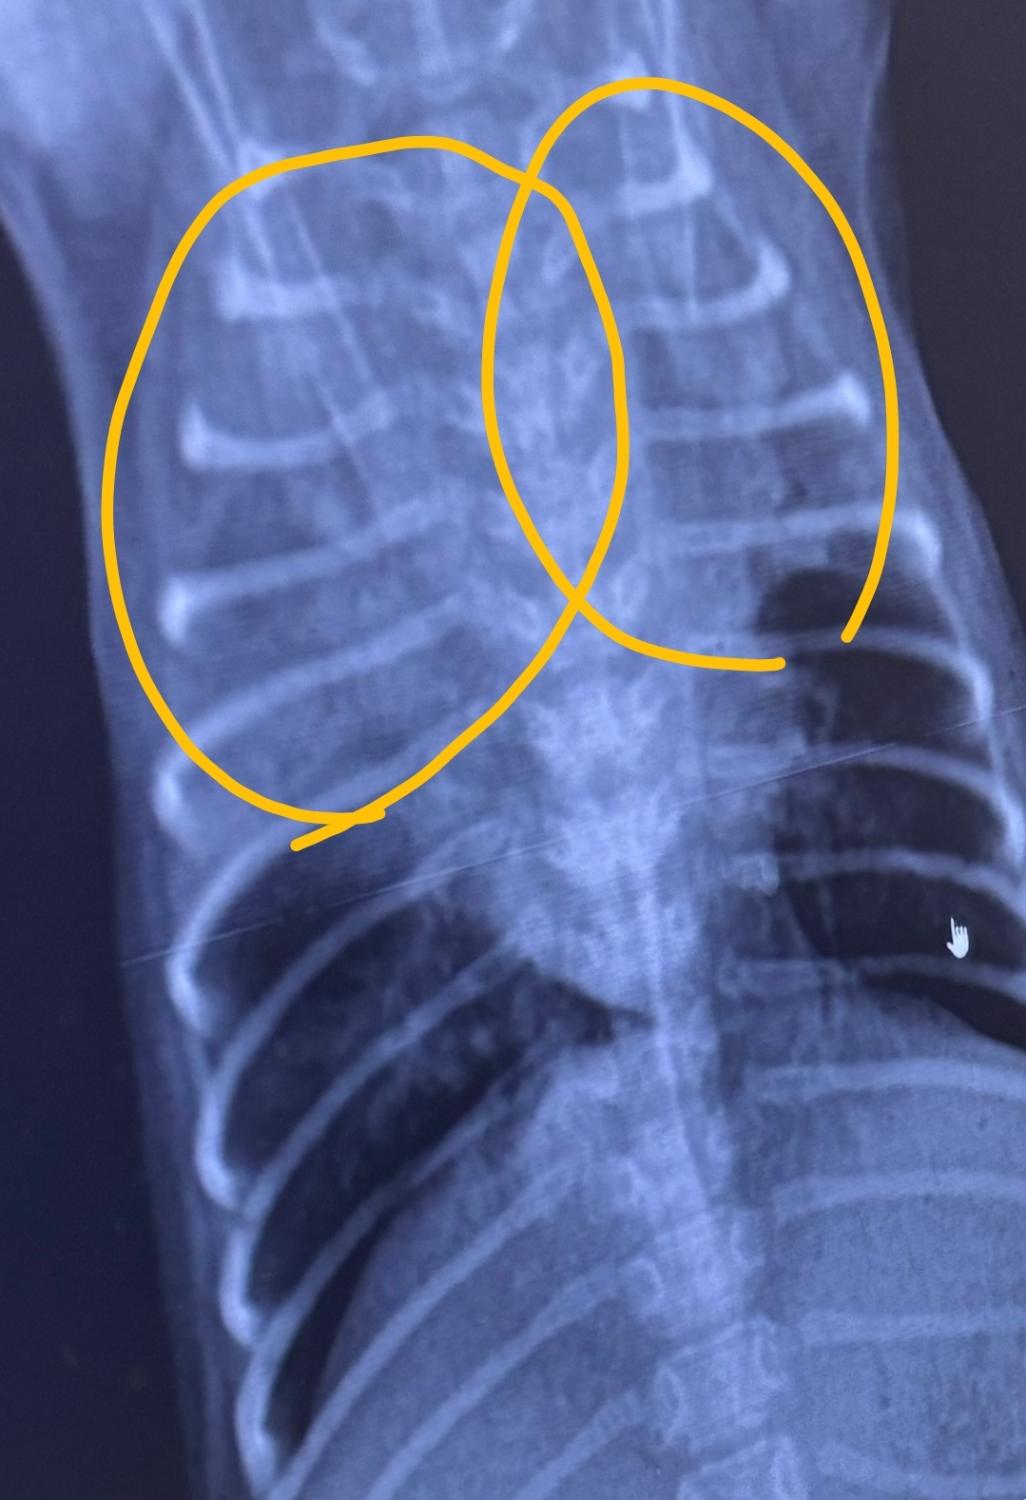

순서대로 2일 간격 엑스레이 사진입니다 ㅠ

점점 안좋아 지는게 맞나요?!

기침은 계속해요.. 의사말로는 마지막 오늘 엑스레이 보고 폐의변화가 있어 숨쉬기 힘들어 할꺼다 하는데 ㅠ 여기가 중국이라서 제대로 치료가 되는지 걱정입니다

폐 전엽부가 다 먹혀버린 매우심한 세균성 폐렴 혹은 인플루엔자 감염이 의심됩니다.

집중적인 처치가 필요한 상태이니 주치의와 잘협의하게 집중 처치하시기 바랍니다.